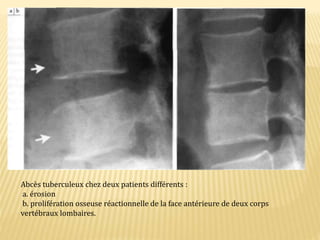

Abcès tuberculeux chez deux patients différents :

a. érosion

b. prolifération osseuse réactionnelle de la face antérieure de deux corps

vertébraux lombaires.

Abcès tuberculeux chezdeux patients différents : a. érosion b. prolifération osseuse réactionnelle de la face antérieure de deux corps vertébraux lombaires.